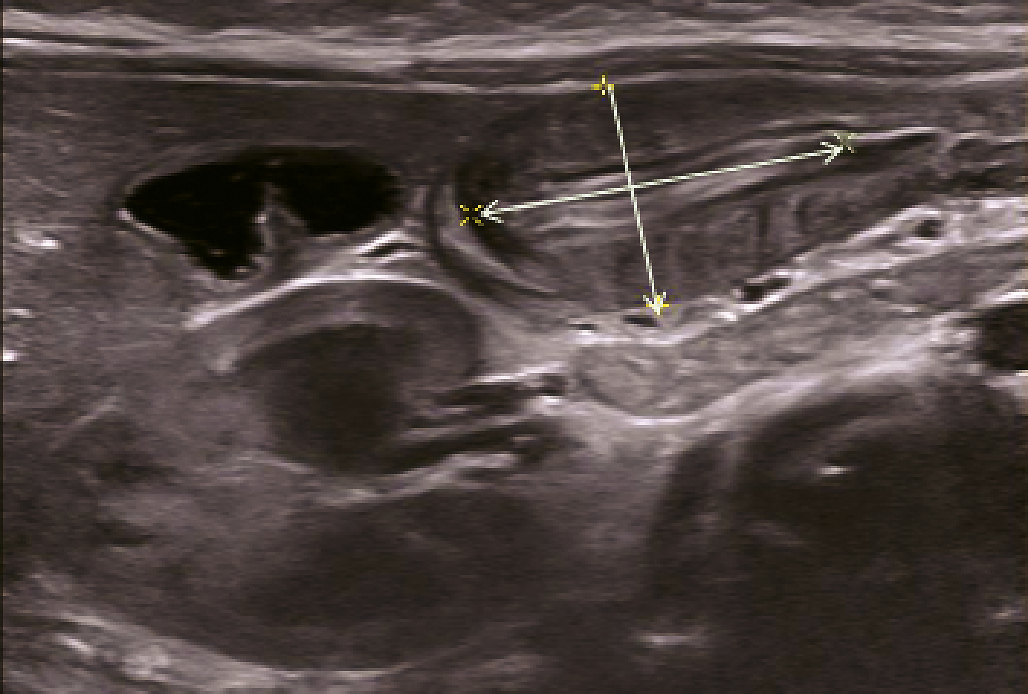

Une radiographie d’abdomen sans préparation (ASP), faite au moins une heure après la dernière tétée, montre un estomac qui reste plein avec un niveau hydro-aérique gastrique, associé à une rareté de l’aération du grêle. Cet abdomen sans préparation n’est plus recommandé depuis janvier 2009 par la Haute Autorité de santé (HAS). Le diagnostic repose sur l’échographie abdominale (fig. 1) qui montre l’olive pylorique avec une image en cible (coupe transversale) ou en sandwich (coupe longitudinale). Les mensurations du muscle pylorique sont augmentées (longueur > 17 mm, diamètre total > 13 mm, épaisseur musculaire > 4 mm). L’estomac est en stase avec de rares passages transpyloriques. En cas de mensurations limites, l’échographie sera refaite après 24 ou 48 heures montrant alors des signes plus francs. Le transit œsogastroduodénal n’est plus réalisé pour le diagnostic de sténose du pylore.